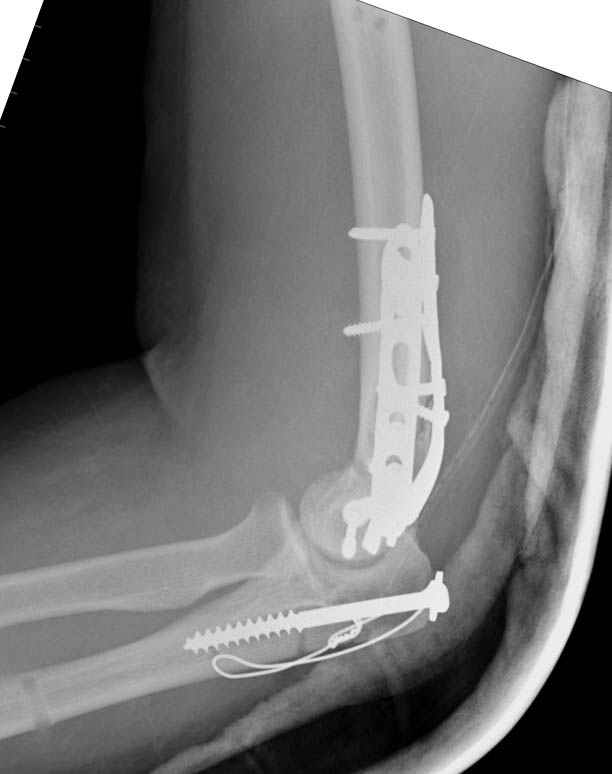

Снимки - во вложении.

Женщина 42 лет, операция через неделю после перелома.

Д-з - открытый перелом мыщелков со смещзением и локтевой кости

без смещения - падение с лошади.

Остеосинтез закрытый (если так можно выразиться), т.е. без

разрезов. Длительность операции - около 1,5 часа со студентом.

6 щелчков ЭОПом.